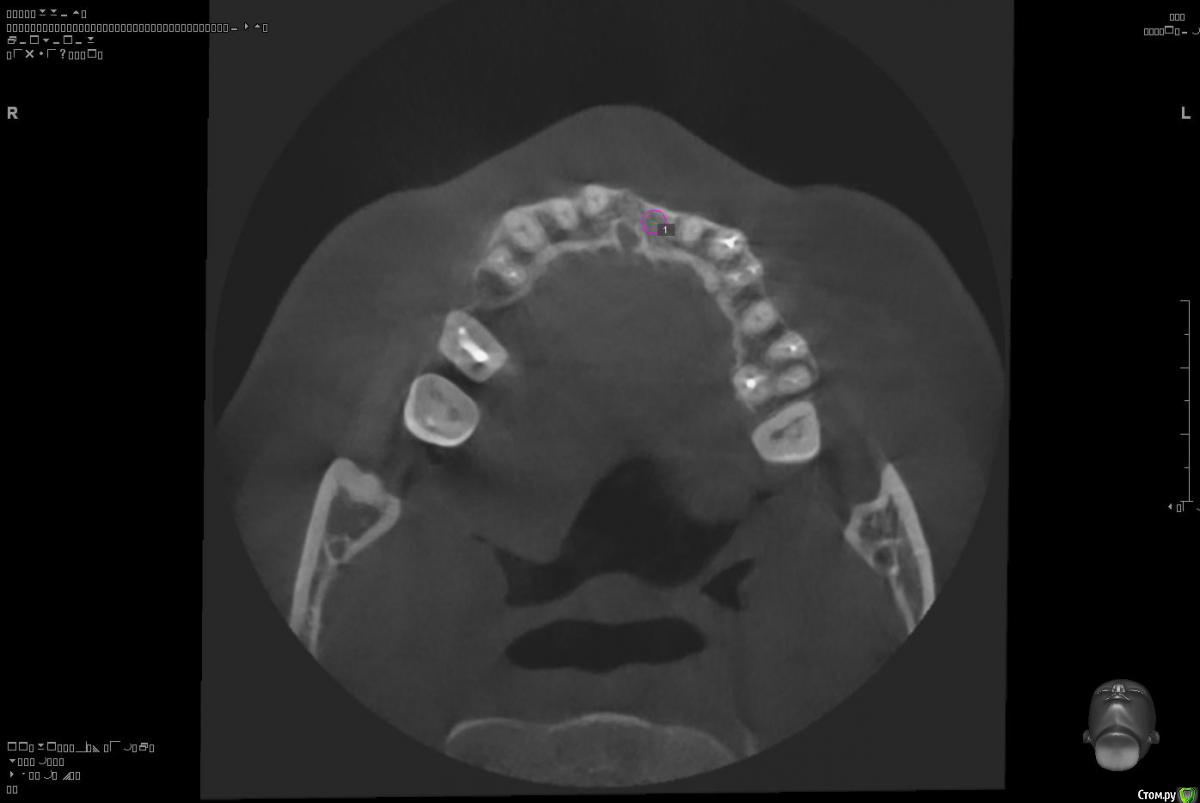

Platon Опубликовано 10 января, 2016 Поделиться Опубликовано 10 января, 2016 Здравствуйте.Помогите с планированием начинающему.Пациентка 38 лет. отсутствует 21. визуально в области 21 провал (фото нет, пока только кт). ходит с акриловой "птичкой"ортопед говорит: ставь, она к эстетике не будет предъявлять претензий))). с чем мне не хочется соглашаться(система ALPHA BIOкак правильно поступить?какие варианты рассматриваю:1. имплантация 3,75 на 11.5 SPI. ,+ временная коронка. Без какой либо пластики.2. костная пластика (мембрана,ксено,) без имплантации, сст, капа на 4 -6мес. потом имплантация + временная коронка3. имплантация, сст , временная коронка С учетом обстановки, прессинга, отсутствия опыта в аугментации, склоняюсь к третьему варианту. заранее спасибо за советы!удачного дня! Ссылка на комментарий